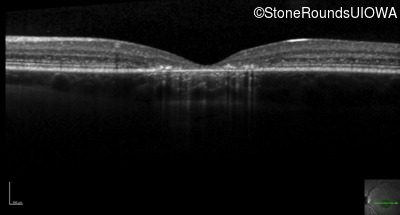

Optical Coherence Tomography - Left - 20/125 -2 sc

Exemplar / OCT Stack